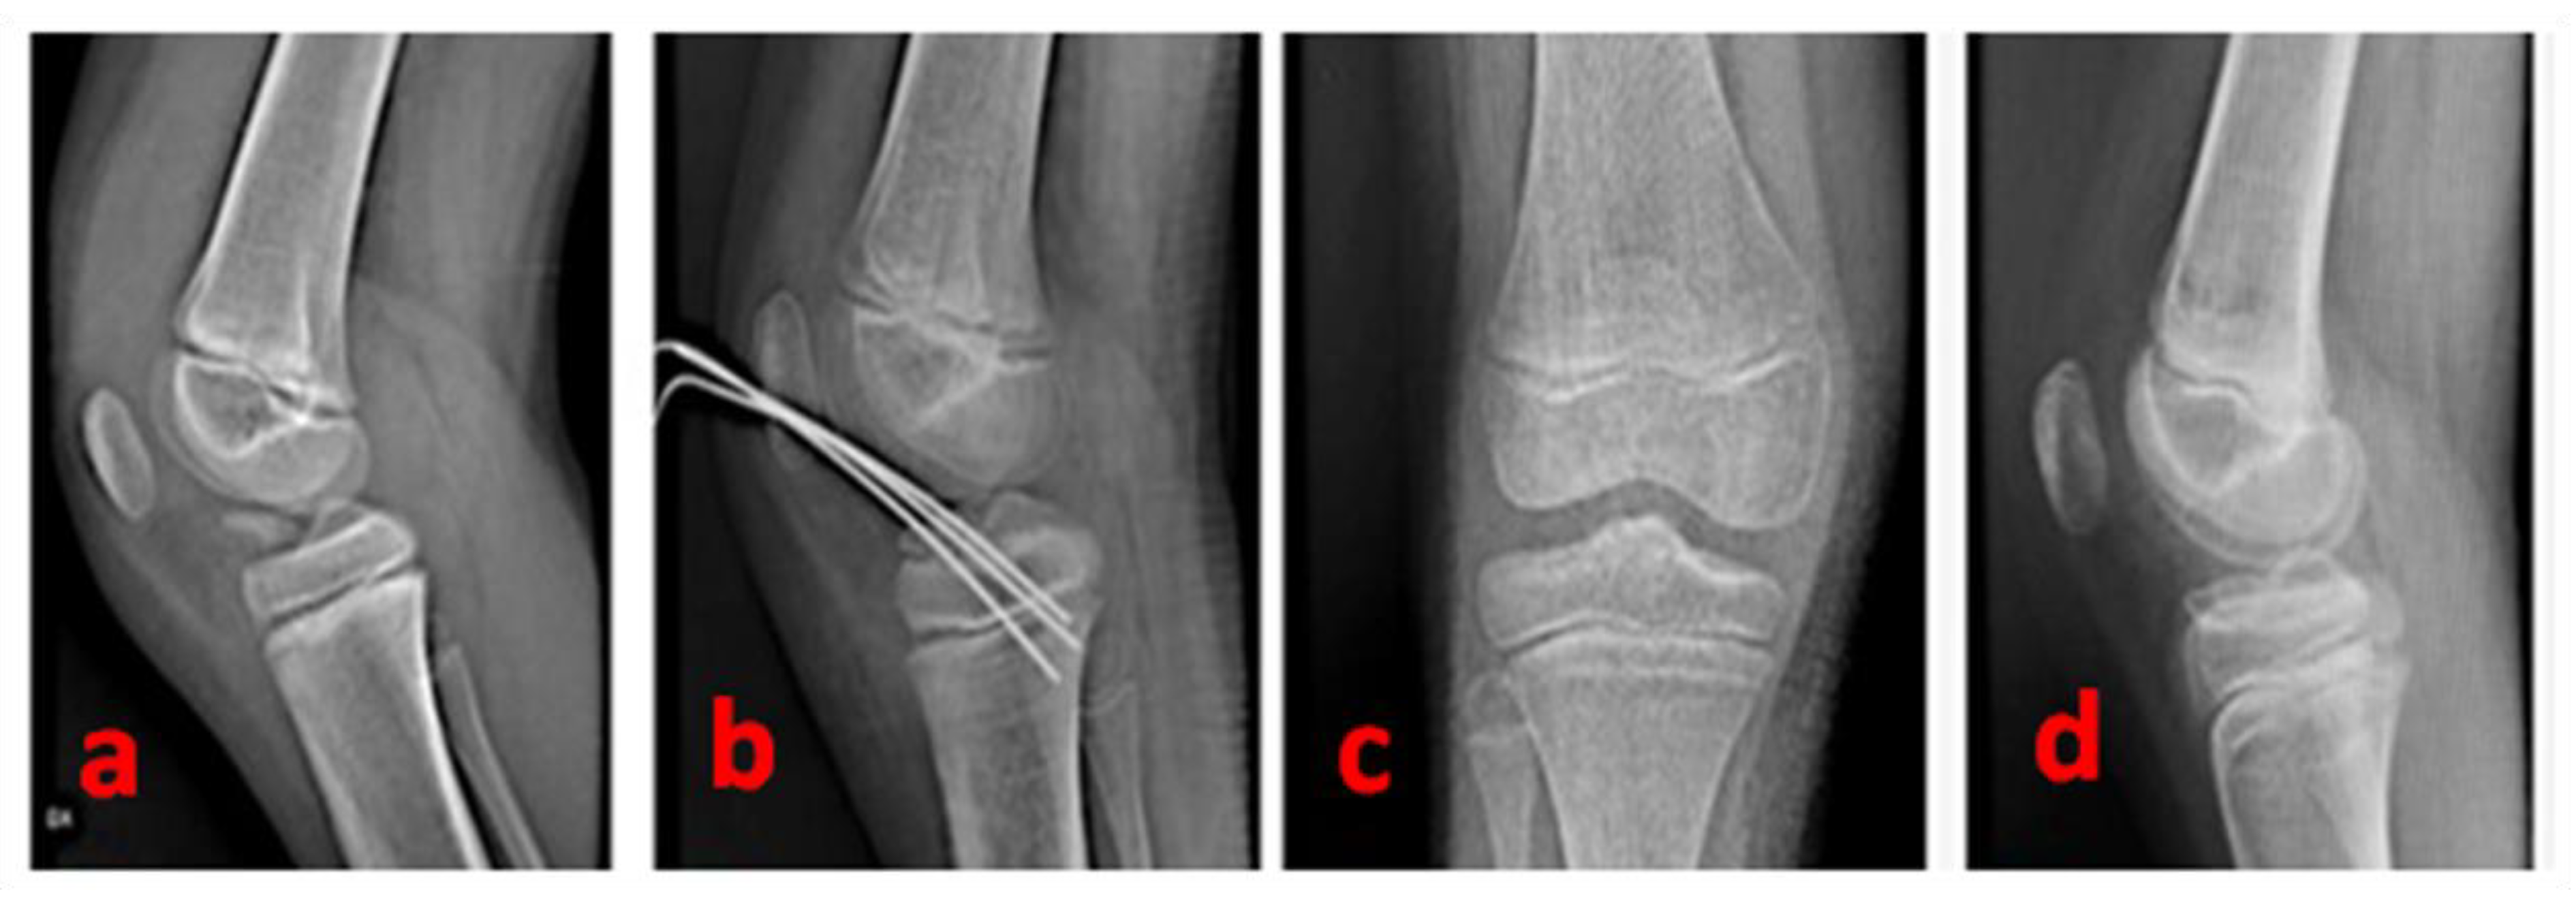

A complete clinical recovery (with a totally stable tibial spine) is generally obtained 3 months after the surgery. At this time, patients can be encouraged to resume sports activities (including skiing or cycling)—(Figure 5 and Figure 6).

Figure 5.

A radiographic summary overview of the right knee of a 9-year-old female patient—(a): pre-operative lateral view of a 3-type TSA; (b): post-operative radiographic control showing the cross-shaped geometry of the Kirschner wires; (c): antero-posterior radiographic control 15 months after surgery; (d): lateral radiographic control 15 months after surgery (complete restoration).